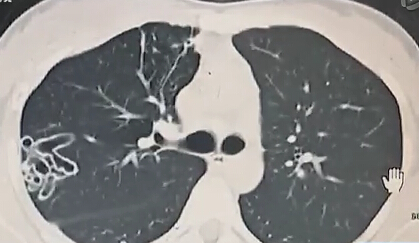

女孩吃小龍蝦 肺部現(xiàn)空洞